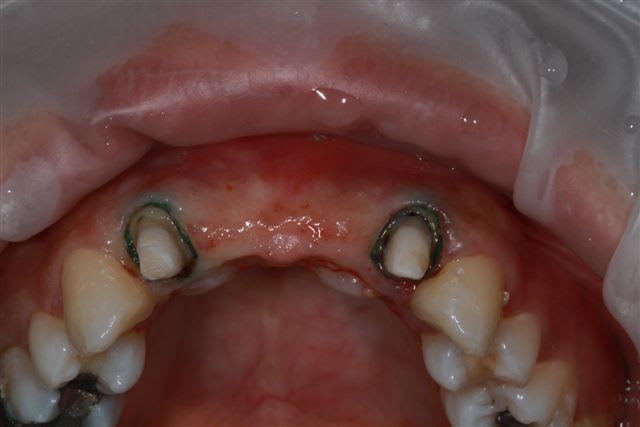

mon idée, après réflexion, bridge provisoire résine, pose de deux implants 11/21 et "sauvetage" de 12/22 donc 4 CCC indépendantes.

Et plus tard si 12/22 se cassent ...2 implants et toujours 4 CCC indépendantes.

Le sauvetage de 12 et 22, pourquoi pas, mais bon, faut voir.

4 implants, c'est général moins jolie (papilles difficile) et comme tu dis manque volume osseux important pour 11-21.

Idéalement, cone-beam pour voir où est la position idéale de l'implant en 3D pour le projet prothétique et ensuite greffer ce qu'il manque.

pour les 4 implants c'est moins joli...çà dépend...l'erreur c'est généralement de vouloir poser du trop gros diamètre et du coup tu ne peux plus respecter parfaitement les espaces inter-implantaires indispensables pour pouvoir recréer les papilles

tu as en plus une perte de longueur de l'arc du fait de la résorption osseuse qui te complique les choses et bien souvent donc, en antérieur tu es obligé d'être dans la configuration 2 ou 3 implants pour pouvoir remplacer 4 dents...